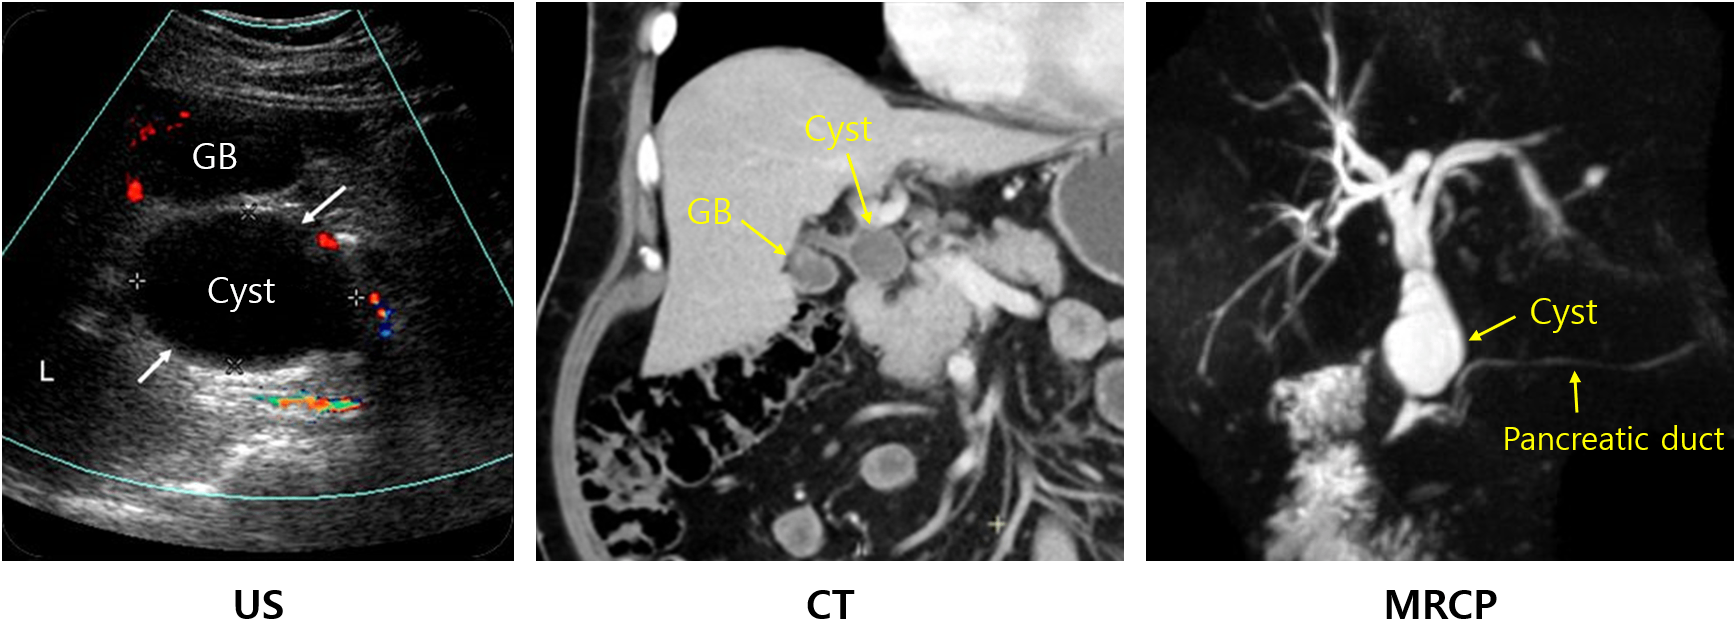

1) 복부 US, 복부 CT: Cyst의 유무, 담관 확장 등을 확인할 수 있음

2) MRCP/ERCP: 담도를 효과적으로 조영함 (distal CBD 및 pancreatic duct와의 접합부는 ERCP로 더 잘 조영됨)